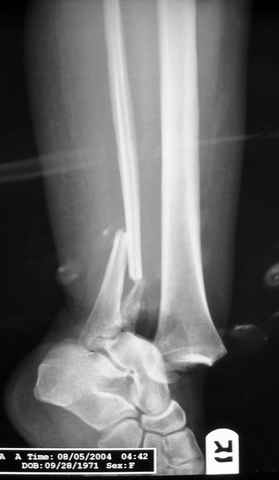

Dear all,40 y.o. man had sustained this terrible fracture falling from a motorbike.

Closed fracture.

We have put his limb in traction.

After some days of traction I would like to insert an external fixator (I think a circular one instead of a monoaxial one, because of the multiplanar situation of the fracture).

This is really Pilon Fx (C3.3; the high energy and the extent of distal tibia comminution are defining it).